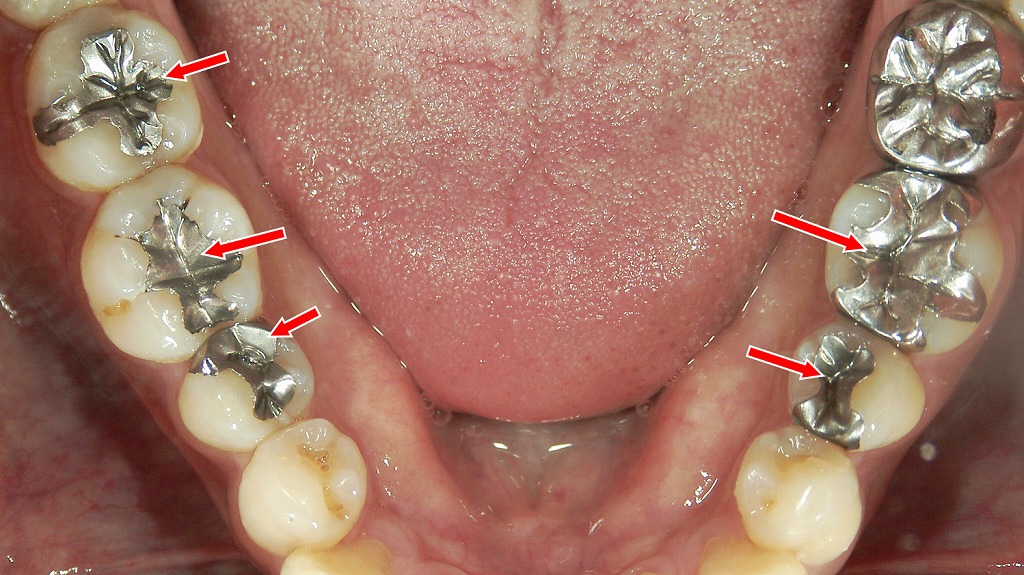

この画像は下顎(下の歯列)を上から見た口腔内写真です。赤い矢印で示された歯には、**銀色の詰め物(メタルインレー)**が装着されています。

🔍 状況の説明

- **金属インレー(銀歯)**とは、虫歯を削った後に金属で成形した詰め物を装着する治療法です。

- 矢印の歯はすべて臼歯(奥歯)で、主に咬合面(噛む面)の虫歯治療です。

- 左右の臼歯にわたって複数の金属修復物が確認され、広範囲に治療歴があることがわかります。

🦷 観察されるポイント

- 適合状態

- 肉眼的にはおおむね適合しているように見えますが、

一部の辺縁に**変色(2次カリエスやセメントの劣化)**が疑われる箇所があります。

- 歯の色調差

- 天然歯と金属のコントラストが強く、審美的にはやや目立ちやすい状態です。

💬 臨床的な考察

- 金属インレーは強度が高く、長期間使用できますが、

経年劣化やセメントの溶解により2次虫歯を起こすことがあります。 - 金属アレルギーや審美性の問題を考慮し、

近年はセラミックインレーやコンポジットレジン修復、CAD/CAMインレーへの置き換えが選択されることもあります。